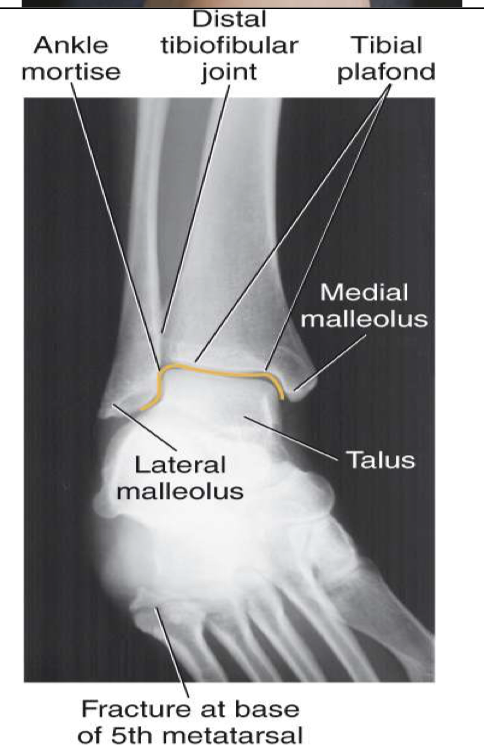

AP Oblique ( Mortise) Ankle

Entire lower limb is rotated 15-20◦ to place intermalleolar line parallel to IR

CR

Perpendicular to midway b/w malleoli

Collimation

Include distal tib/fib (⅓ ) and proximal metatarsals, especially the base of the 5th medially

Evaluation Criteria for AP mortise ankle

• Entire ankle mortise open

Medial , lateral & superior aspects

• Distal ⅓ of tibia and fibula demonstrated

Little, if any, overlap of distal tib/fib

• Proximal ½ of metatarsals included

• Optimal exposure factors